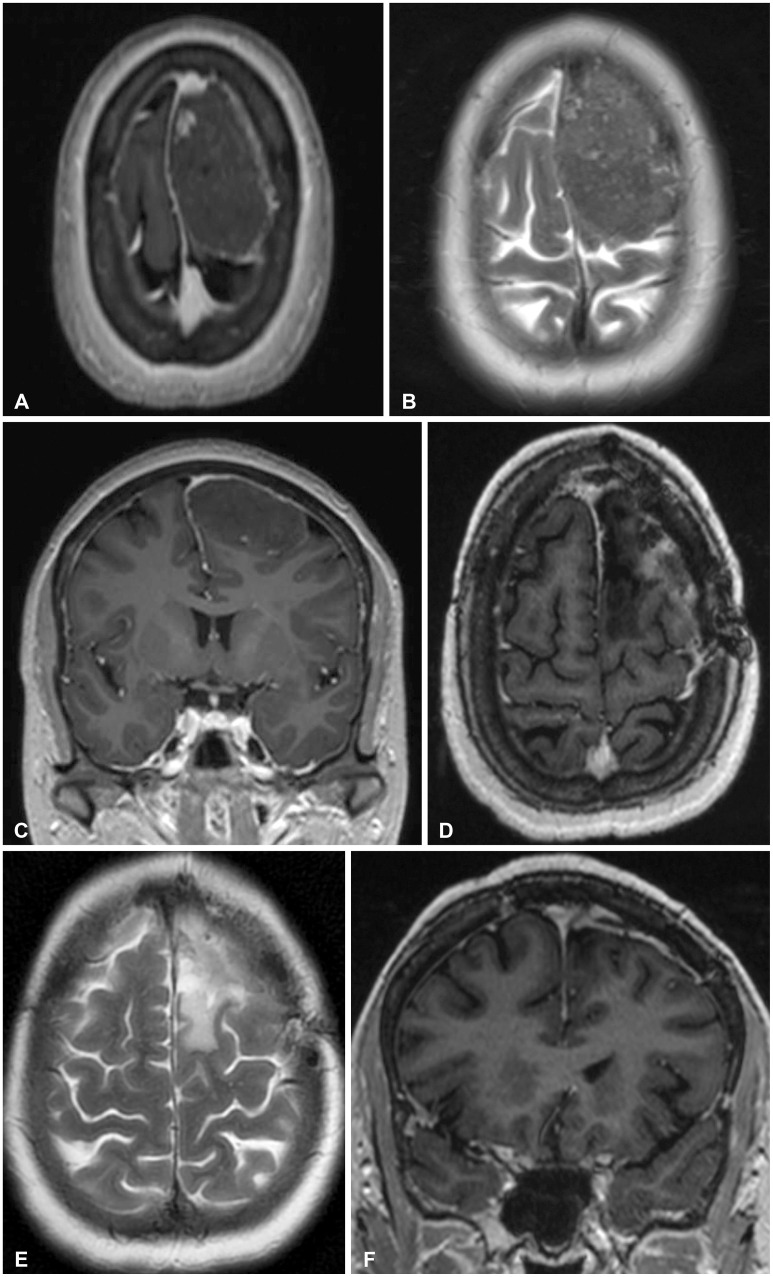

颅内软骨瘤是一种良性肿瘤,起源于硬脑膜或硬脑膜褶皱、脉络膜丛或脑实质的胚胎软骨。它是罕见的颅内,但当它确实发生时,它主要位于颅底。在颅内软骨瘤队列中,镰旁位置是最罕见的。我们报告一个具有挑战性的诊断和成功的管理这种罕见的颅内镰旁软骨瘤的53岁女性患者。

Intracranial chondroma is a benign tumor arising from the rests of embryonic cartilages in the dura or dural folds, choroid plexus or the brain parenchyma. It is rare intracranially, but when it does occur, it is predominantly located at the skull base. Among the cohort of intracranial chondroma, the para-falcine location is the rarest. We report a challenging diagnosis and successful management of this rare intracranial para-falcine chondroma in a 53-year-old female patient.